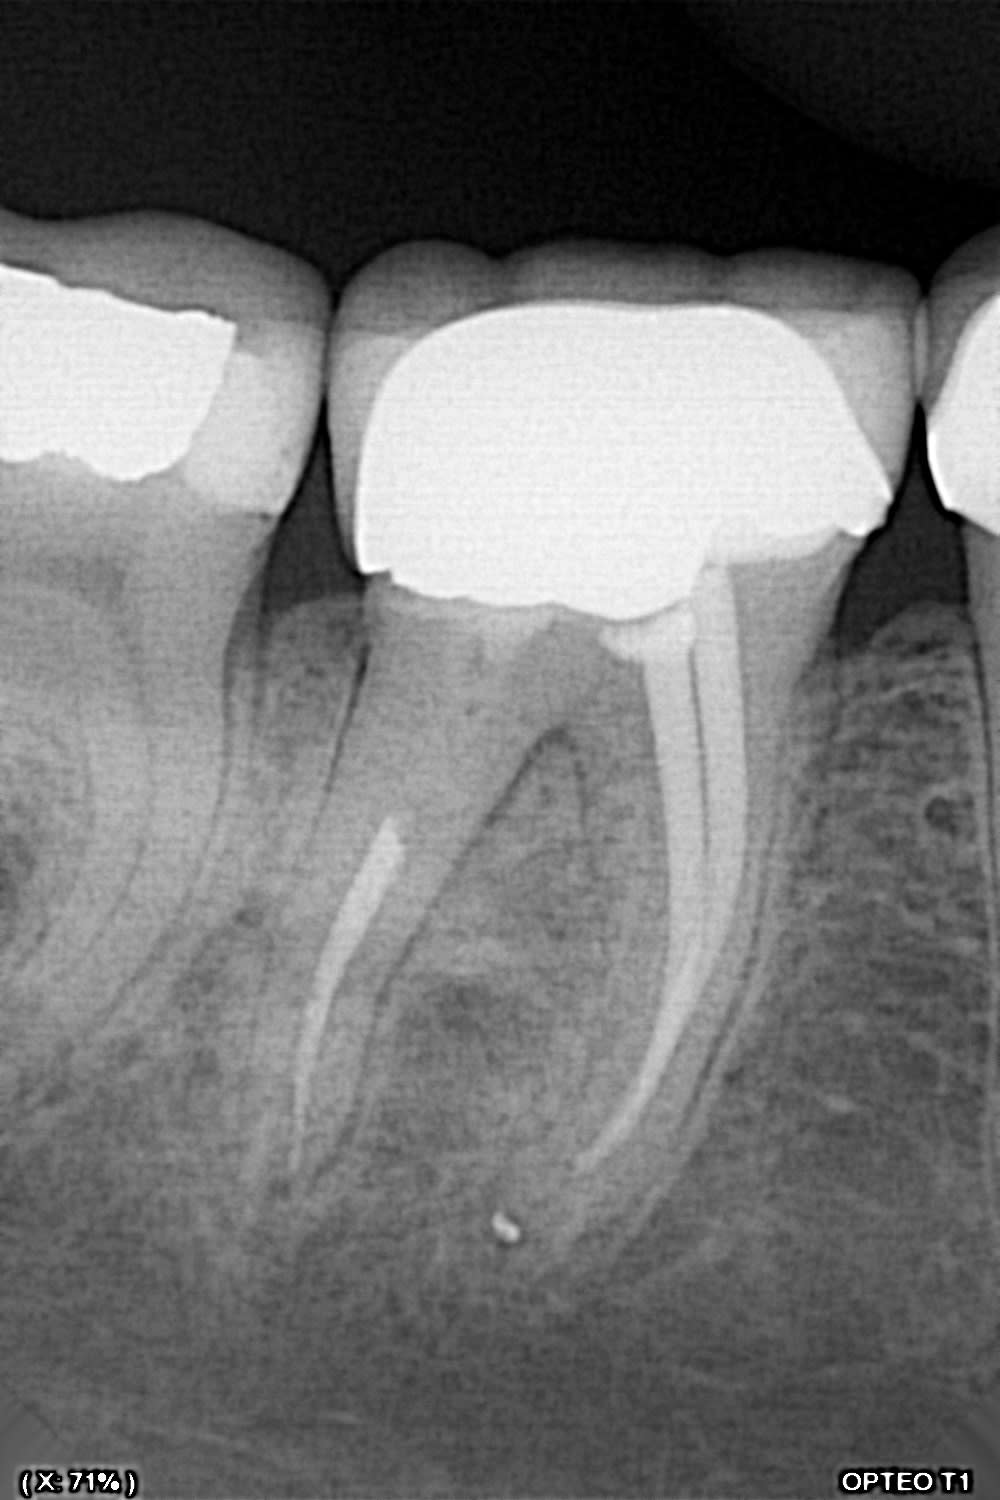

Moi j'ai fait ça la semaine dernière (et je ne suis vraiment pas fier).

Pas de douleurs pas de saignement au forage. La patiente me dit: ah, j'ai un peu mal quand j'appuis dessus...

Que feriez vous?

Perfo1 anwzvp - Eugenol

Finalement, séance suivante: mise en évidence d'un saignement dans le logement du tenon.

Obturation à la biodentine que j'ai fait "descendre dans le logement du tenon " avec un insert fin sans eau.

Disparition des symptômes la semaine suivante.

Contrôle à 6 mois, dent asymptomatique, radio encourageante.